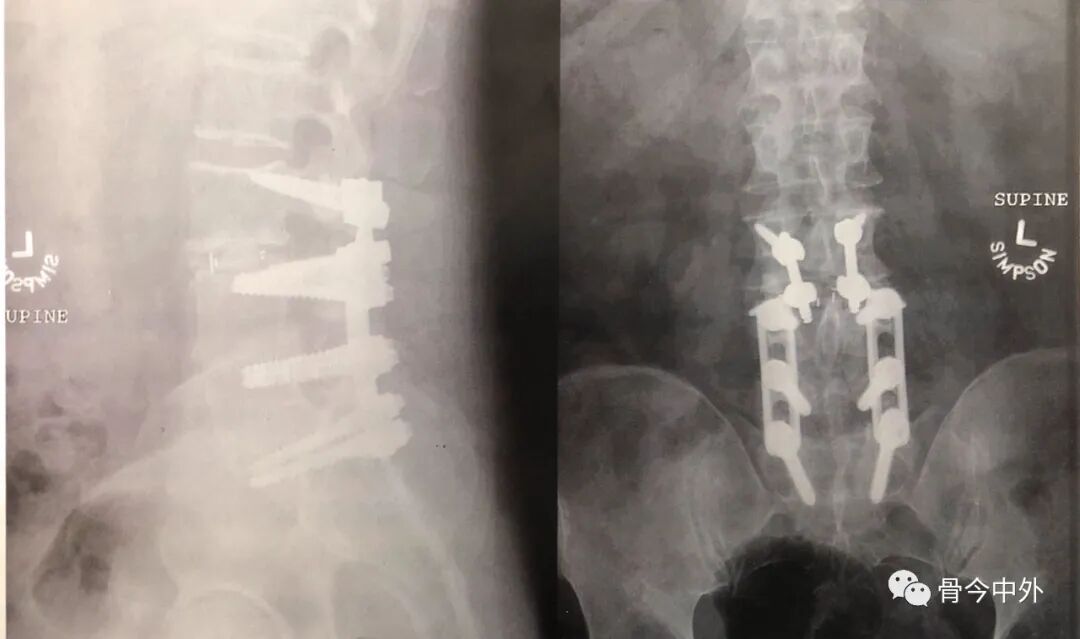

图2 在先前的L4~S1传统椎弓根螺钉固定的基础上行L3~L4皮质骨螺钉的术后正位(右)和侧位(左)X线片,行L4皮质骨螺钉植入时,不会干扰原有的椎弓根螺钉。